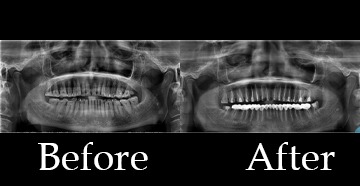

Before and after pics of some of the patients treated at Balani Hospital.